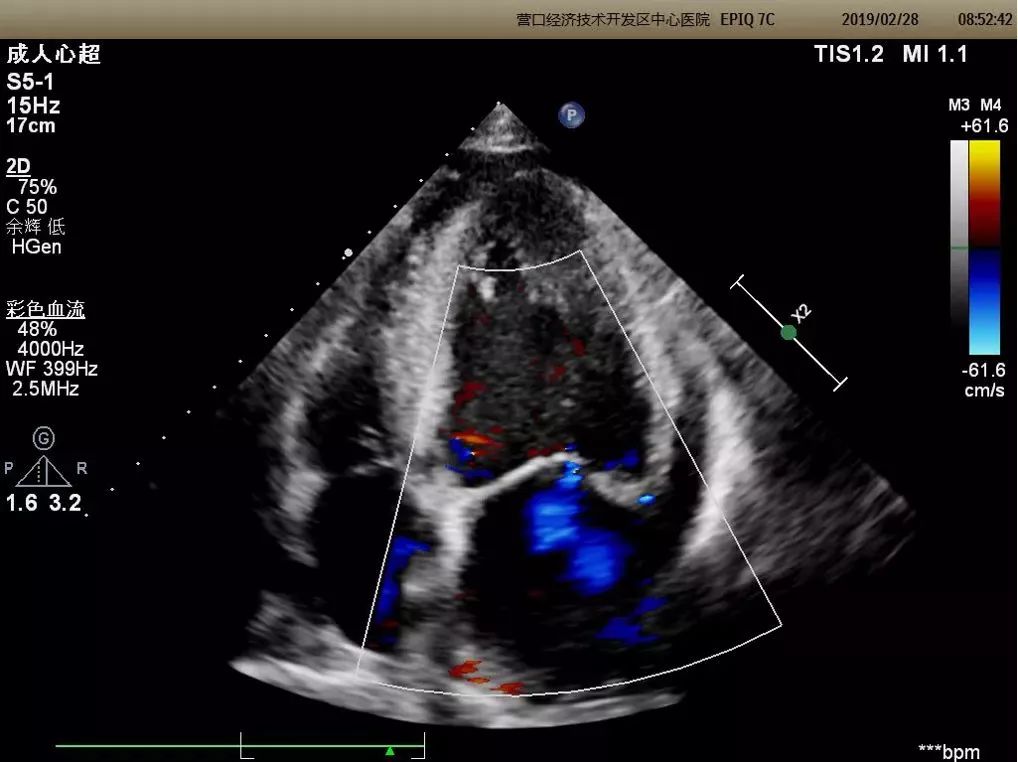

心脏三维超声成像

能够整体、直观的获得心脏内部结构图像,医生可多角度、多切面观察,适用于瓣膜病、先天性心脏病等疾病,使超声诊断更加准确。

二维成像

三维成像